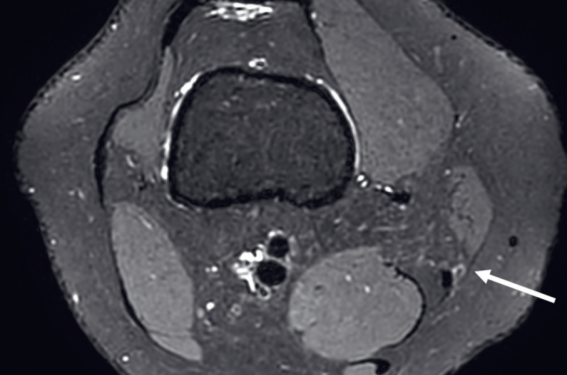

Les malformations veineuses (MV) et les anomalies fibro-adipeuses vasculaires (FAVA) sont des affections vasculaires congénitales qui, bien que bénignes, peuvent être invalidantes en raison de douleurs chroniques et d’une altération de la qualité de vie des patients. Traditionnellement, la prise en charge repose sur des options thérapeutiques variées, notamment la sclérothérapie et la chirurgie. Cependant, ces traitements présentent certaines limites, telles qu’un risque élevé de récidive, une efficacité parfois limitée et des complications postopératoires potentielles(1,2). Parmi les alternatives émergentes, la cryoablation percutanée (CA), une technique mini-invasive guidée par l’imagerie, se distingue par son efficacité et sa capacité à traiter les lésions en minimisant les risques pour les tissus environnants(3,4).

Principe et technique de la cryoablation La cryoablation repose sur l’utilisation de sondes cryogéniques qui appliquent des températures extrêmement basses (- 40 à – 80 °C) directement sur la lésion. Cette procédure entraîne la formation de cristaux intracellulaires provoquant une rupture des...